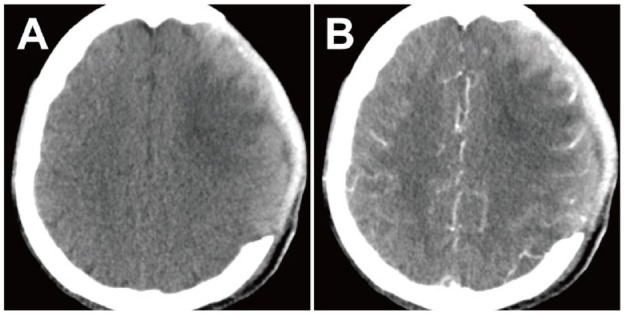

Case presentation: A 48-year-old man presented with a 9-hour history of alalia and right limb hemiplegia. Noncontrast computed tomography (CT) revealed a hematoma in the left frontal lobe, while CTA showed a spot sign within the hematoma, leading to a diagnosis of frontal lobe hemorrhage. During the surgical procedure, a blood clot was removed, revealing the presence of 3 mm of saccular tissue resembling an aneurysm. The process of exposing its complete form resulted in its rupture and bleeding. The location of this tissue at the top of the hematoma cavity corresponded to the CTA spot sign. Pathological examination confirmed that the characteristics of the tissue wall were consistent with those of a pseudoaneurysm.